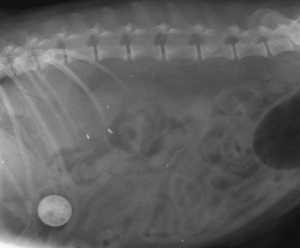

Hyrje » Për veterinerët » I mbrojtur: Kafshët e shoqërimit » Helmimi nga zinku tek kafshët shtëpiake » qeni hengri monedha

Botuar më te 300 × 248 në Helmimi nga zinku tek kafshët shtëpiake.